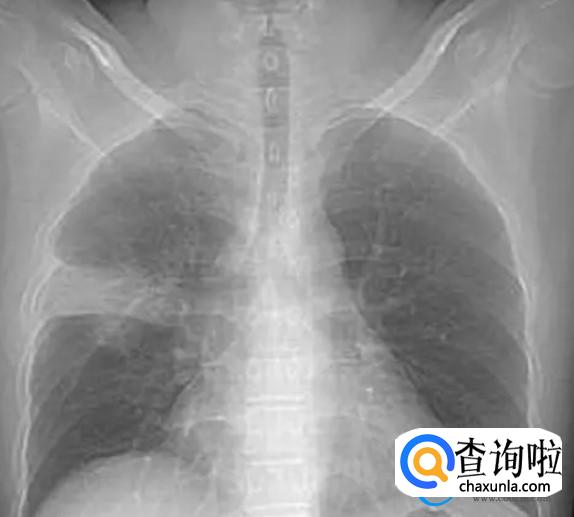

白肺产生之后,其实就是日常生活中所说的重症肺炎。一般白肺在检查时主要通过X光检查肺部,通过检查之后,可能会显示出一大片白色的泡状,从而被称之为白肺,白肺一旦形成之后是非常严重的,特别是一些老年患者。

一般形成白肺之后,也就预示着肺部已经被炎症所广泛的浸润,目前引起白肺的原因可能有多方面相对来说也是特别复杂的。一旦形成白肺之后,可谓是来势凶猛,在临床诊断方面是比较困难的,一般在治疗白肺时,也需要及时的找到白肺的具体原因,并且通过多种方式综合有效的进行治疗。